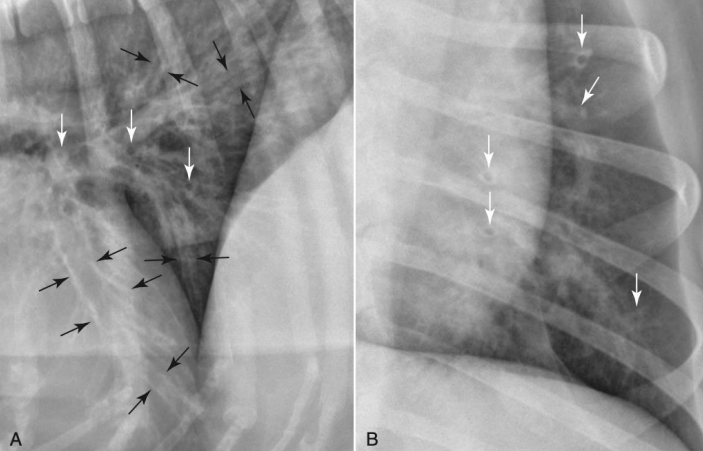

Lobar sign

alverolar pattern이 한 엽에만 진하고 뚜렷하게 나타났을 때.

흰색 부분에 alveolar pattern 뚜렷

Alveolar pattern

- 언제?

- 무기폐, 폐렴,. .

- 생명과 관련 있는 질병과 밀접하여, 가장 중요

perihilar region에서 pattern- 고양이 : 전반적으로 지저분하게 찬 모습

- 고양이 폐수종의 전형적 : 좀 지저분하게 나타남, 다른 패턴과 헷갈림

- 폐가 쪼글어들어

- 오연성 폐렴 (